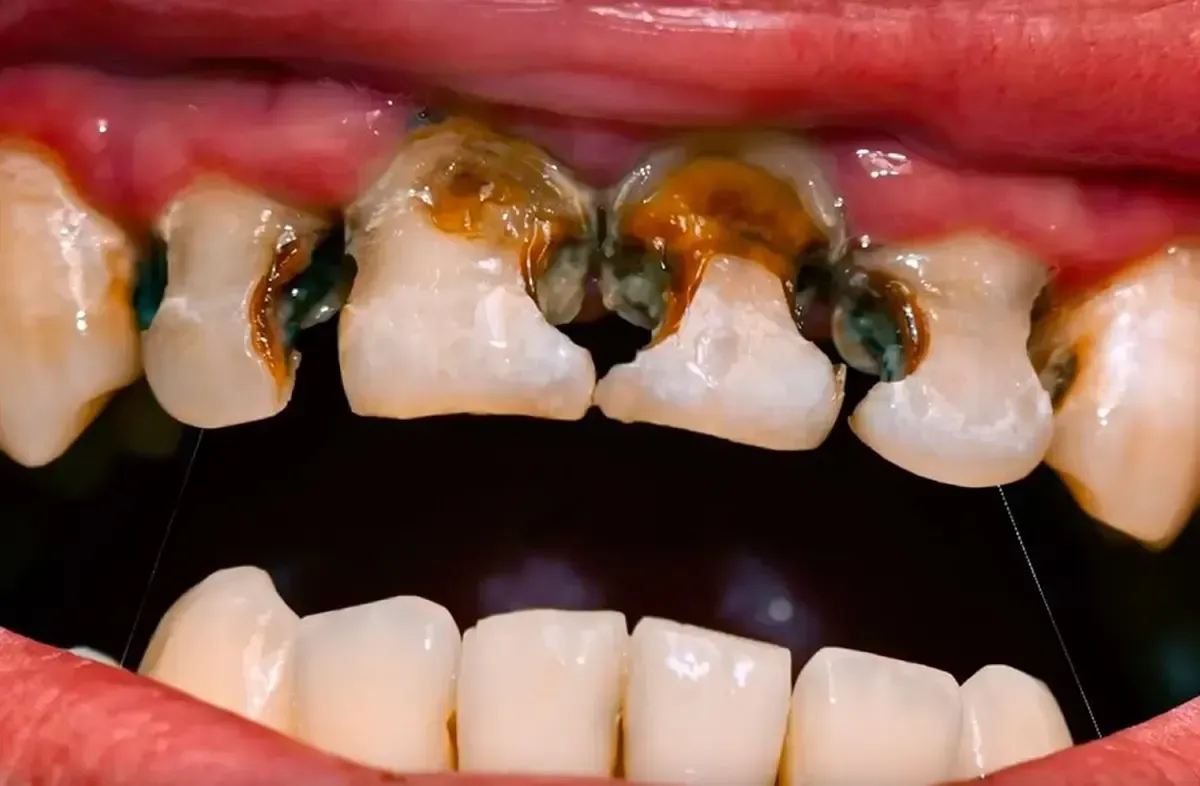

There are a number of reasons why a patient could have a dental infection. Any type of infection can have a detrimental effect not only to the surrounding area but to your overall health as well. Abscessed teeth or gum swelling should be treated with antibiotics and a treatment solution from our dentists ASAP. Do not put this off. If the swelling gets too close to your eye or throat, please quickly get yourself to an emergency room for immediate care.